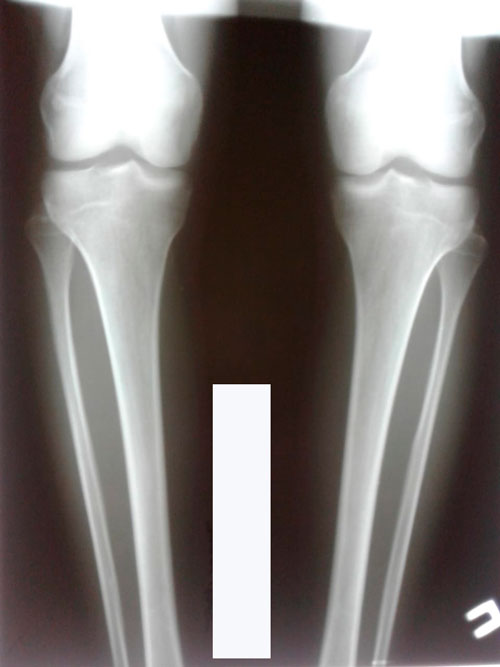

Исходник - 22 года. Павлодар.

Дата операции - 19.06.2018г.

Ротация справа.

Рентген в 60 дней.

Всё идет по плану, следующий рентген в 90 дней.

Дата снятия аппаратов - 15.10.2018г.

Срок лечения - 115 дней.